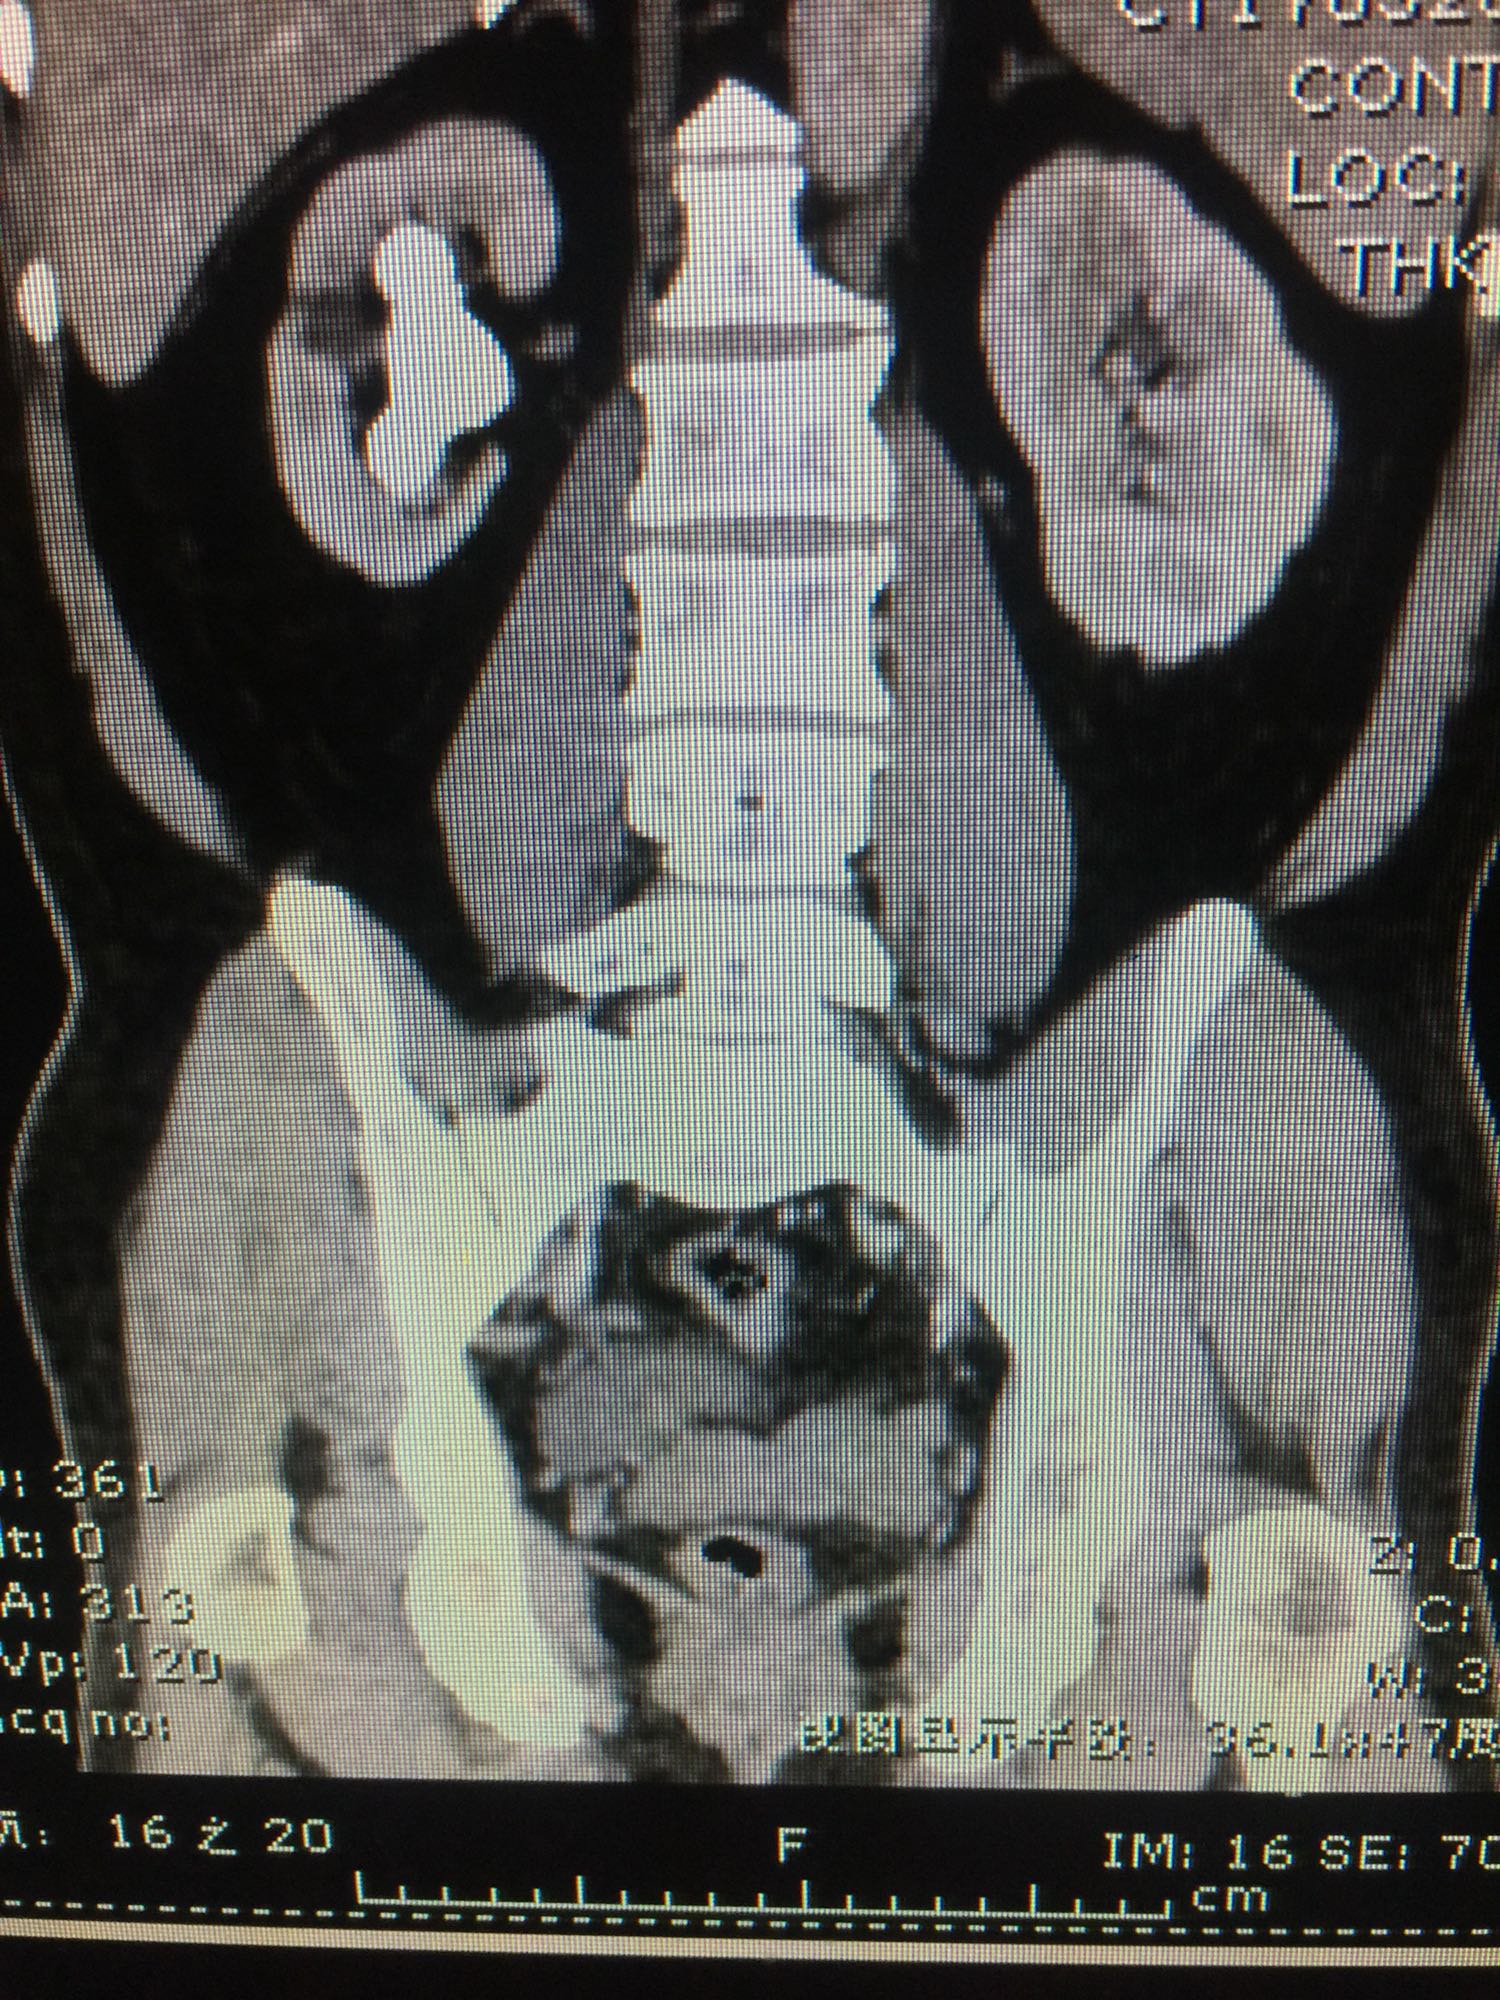

60岁男性 既往无高血压糖尿病等病史 检查发现右侧肾结石10年 10年前检查发现右侧肾结石,直径约1厘米,未给予正规治疗,近日来我院门诊,行彩超发现右肾多发结石,进一步治疗入院。

查体:双肾区无叩压痛,膀胱区无叩压痛,无叩浊,前列腺二度,质地中等,无压痛,无结节。CTU提示右肾铸型结石。ECTL 40,R14.5

右肾铸型结石 予以经皮肾碎石治疗,术后复查平片未见结石残留。